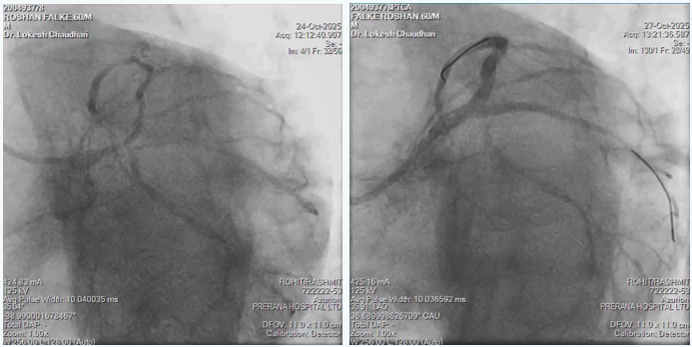

In view of multiple comorbidities and patients preference, high risk complex multi-vessel PCI (Including RCA-ISR-CTO & LM-LAD-LCX bifurcation) was planned and done as per plan under local anesthesia from right radial artery access as CT aerogram showed diffuse peripheral vascular disease starting from abdominal aorta extending into bilateral femoral arteries.

- Complex multi-vessel disease done through 6F Radial access

- RCA-ISR-CTO opened using CTO techniques via 6F catheter

- LM-LAD-LCX bifurcation done using modified MINI-CRUSH technique through 6F catheter

- Entire procedure was done with 140 ml of visipaque without causing any worsening of renal function.